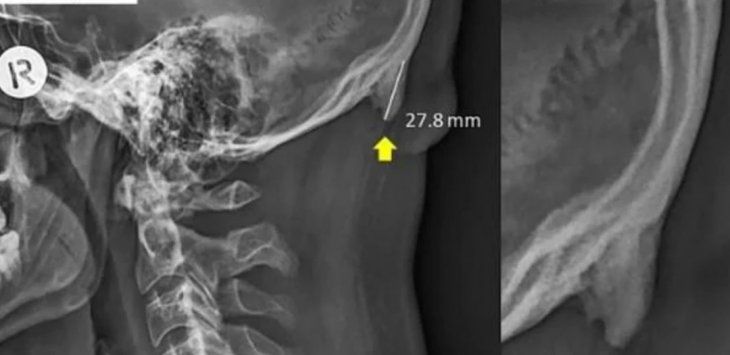

Es una protuberancia que aparece en la parte posterior del cráneo. Se debe a la mala postura que se adopta para revisar el contenido del teléfono.

Los usuarios de celulares se encorvan varias veces al día para revisar sus celulares. Ese movimiento desarrolla "espigas óseas" en la parte posterior del cráneo.

Cada vez son más las personas que desarrollan esta protuberancia, y se la deben agradecer al uso del celular. Gracias a la postura que se utiliza para chequear los móviles, la estructura ósea se va modificando para sostener mejor la cabeza.

Según explican los investigadores, es muy poco probable que estos bultos causen efectos dañinos. Sin embargo, aclararan que una vez que se desarrollan es posible que nunca desaparezcan.